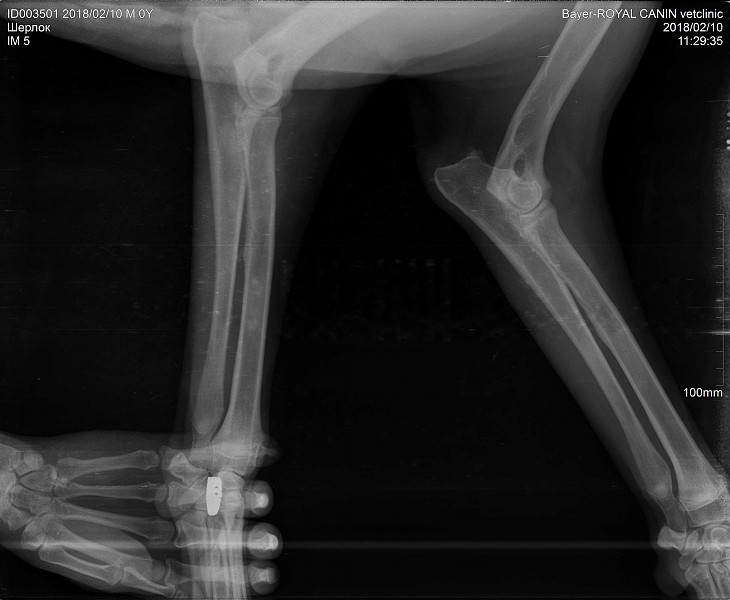

Рентген Задней Лапы Кошки: Нормы и Диагностика